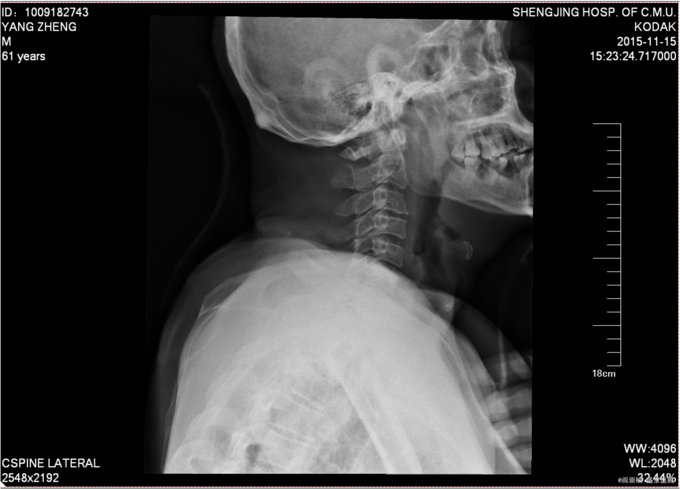

患者于2015年11月13日15:30左右因在工厂2米高管道上作业不慎坠落致颈部疼痛,四肢活动受限,受伤后被家人送入当地北台镇医院,输一袋葡萄糖液,转入本溪二院,行口腔科、眼科缝合行X线检查,头颅ct检查。患者及家属为求系统治疗,急来我院,急诊予以行辅助检查,提示:颈4-6棘突骨折,颅骨多发骨折;急诊以“颈椎外伤”为主诊断收入我科。病来患者一般状态无头晕及头痛,,无恶心及呕吐 ,留置导尿中。

前额部敷料包扎中,打开敷料见右眉处7cm大小创口已缝合,无渗出,前额处可见一5cm大小创口已缝合,颈领保护中,触痛。双手感觉减退。患者平乳头以下触觉存在,痛觉及运动消失。屈肘肌力(R4,L4),伸肘肌力(R0,L0),手掌掌屈肌力(R0,L0),手掌背伸肌力(R0,L0)。双手握力(R0,L0)。髂腰肌肌力(L0级,R0级),伸膝力(L0级,R0级),足背伸力(L0级,R0级),足跖屈肌力(L0级,R0级),神经反射:BCR:L(-)R(-),TCR:L(-)R(-),肱桡肌反射:(-)R(-),PSR: L(-)R(-),ASR: L(-)R(-),Hoffmann Sign:L(-)R(-), Babinski Sign L(-)R(-) 双侧桡动脉、足背动脉可扪及搏动,末梢血运良好。